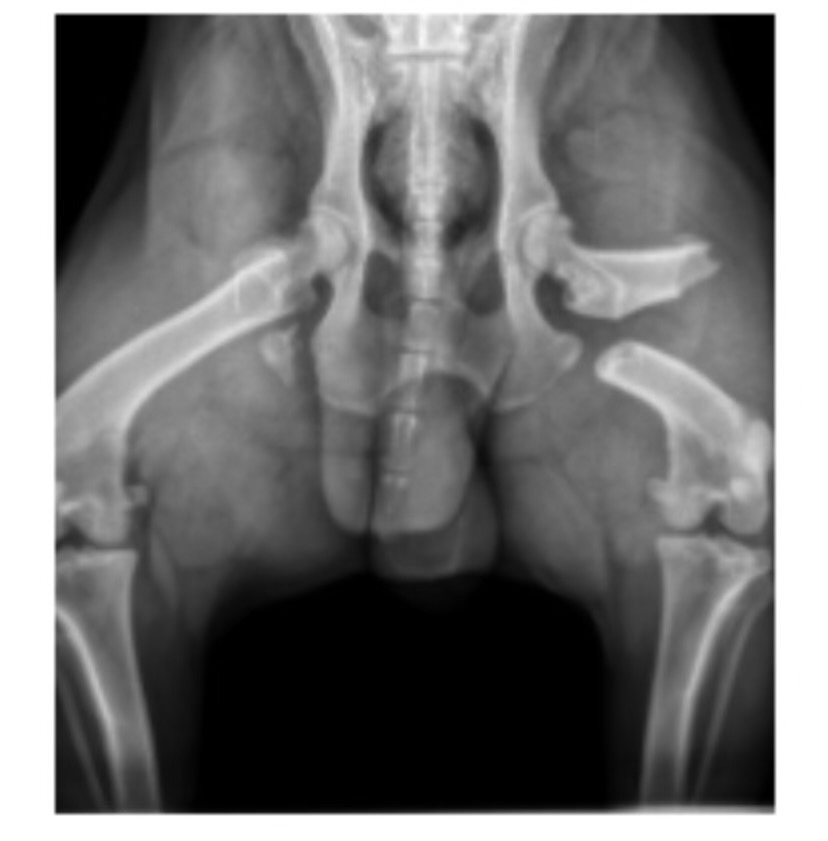

Recently, Boogie was hit by a car and left on the side of the road without us. The accident broke his back femur, and now he needs urgent surgery to recover. Euthanasia is not an option for our family—Boogie loves life too much, and we love him just as fiercely. Right now, I can see how sad he is that he got himself into trouble, and I feel responsible for allowing him to get into this situation. I can feel his soul—he just wants to be himself again. He’s been confined to lying on his side, and even with his medication, he is so uncomfortable. It breaks my heart that money is keeping us from getting the help he needs.